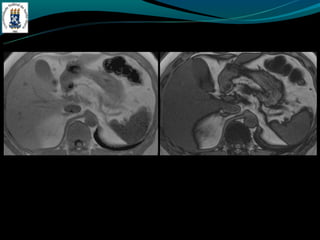

TROMBOSE DA VEIAPORTA -Complicação de cirrose -Invasão ou compressão tumoral -Hipercoagulabilidade -Inflamação -Incidência de 5% na hipertensão portal e próximo de 30% no CHC -TC: Esplenomegalia, formação de colaterais, ascite, e pode ter alta atenuação na fase arterial. -RM: trombo agudo hiper em T1 e T2, crônico hipo em T1 e hiper em T2.

• 26.